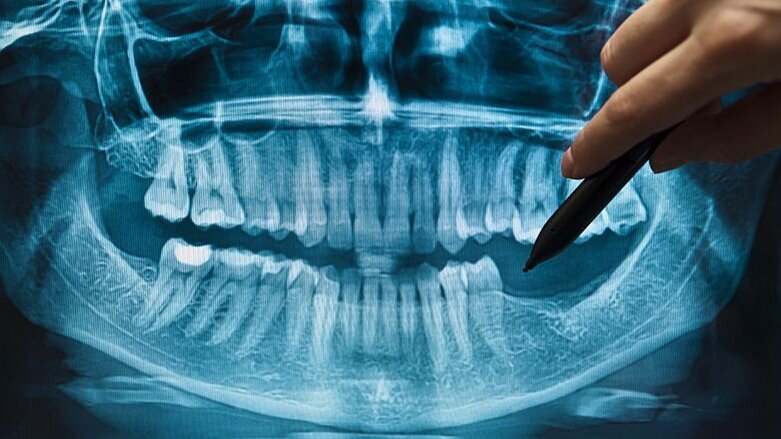

UTRECHT – De concepttekst voor de nieuwe richtlijn Tandheelkundige radiologie is gereed en staat open voor commentaar. Dat meldt beroepsvereniging KNMT.

Een actualisatie van de oude richtlijn uit 2015 was nodig omdat de stralingswetgeving op 6 februari van dit jaar op onderdelen gewijzigd werd. Het Besluit basis-veiligheidsnormen stralingsbescherming (Bbs) vervangt het Besluit stralingsbescherming (Bs). Ook zijn een aantal ministeriële regelingen aangepast en samengevoegd.

De voorliggende conceptrichtlijn ‘vertaalt’ de aangepaste wetgeving naar de tandheelkundige radiologische toepassing. Naast de wetteksten zijn daartoe ook Europese richtlijnen geraadpleegd en is advies ingewonnen bij experts uit het veld.

Met de actualisatie vervalt niet alleen de oude richtlijn Tandheelkundige Radiologie maar ook het KNMT-standpunt over Cone Beam Computed Tomography: CBCT in de mondzorg, dat dateert van 2012. De nieuwe inzichten hieromtrent zijn ook meegenomen.